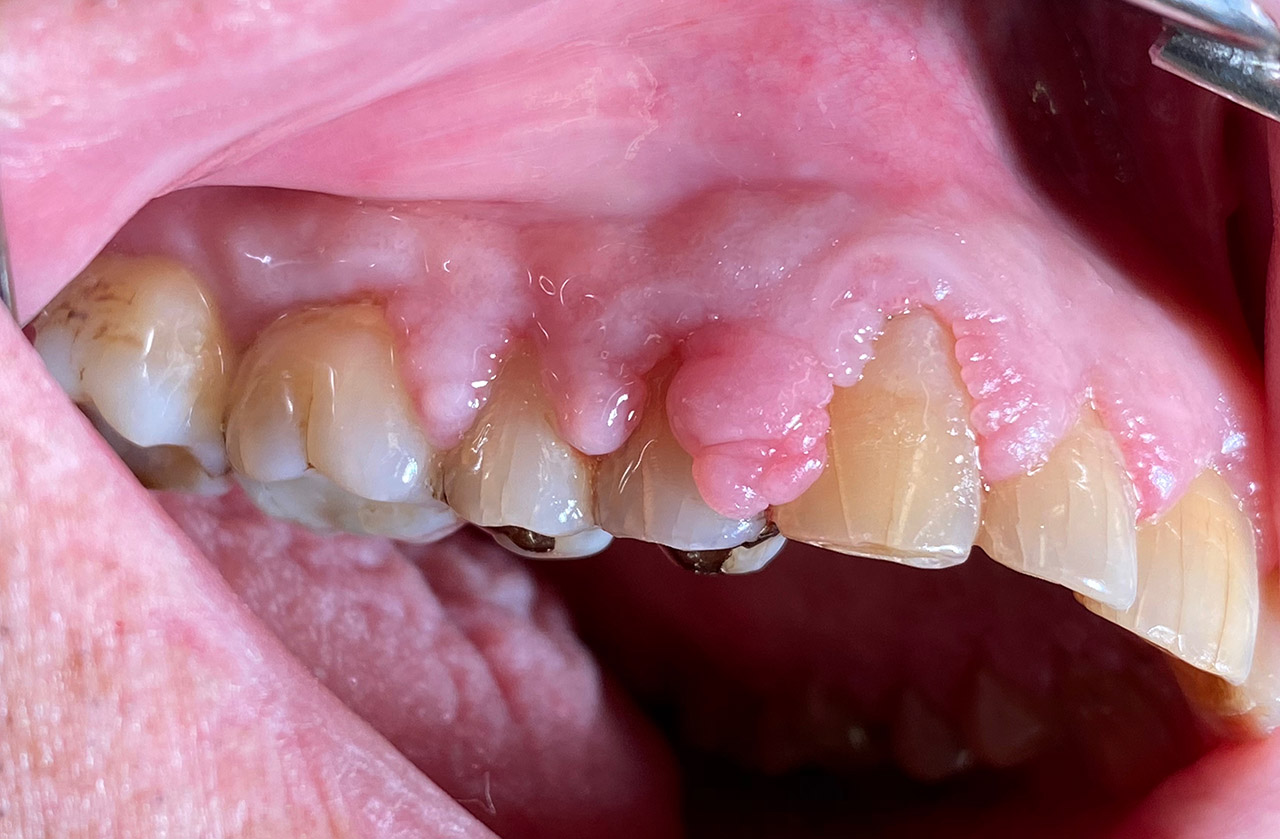

Parodontologie/Gingivahyperplasie:

Diagnose: Gingivahyperplasie durch Medikamente (Blutdrucksenker), unzureichende/nicht mehr mögliche Mundhygiene und überstehende Füllungen.

Therapie: Gingivektomie und anfinieren der Füllungen. Letztes Foto 1 Woche postOP.